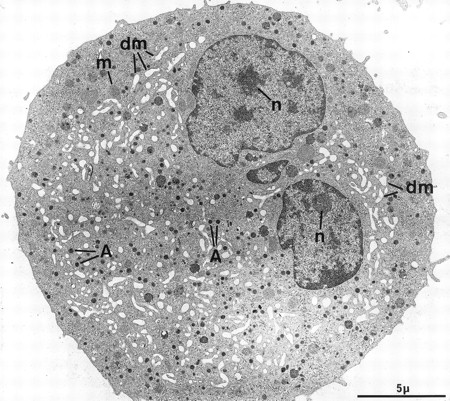

At electron microscopy, apart from the high proportion of megakaryocytic cells in the cultured population (contaminated by a few macrophages and basophils), mature MKs could be divided into two main categories. The first population consists of fully mature, resting MKs and is composed of large cells with a smooth surface (Fig 2). The nucleus displays several rounded lobes, with abundant euchromatin and prominent nucleoli. These MKs have abundant cytoplasm, numerous α-granules randomly scattered throughout the surface, only a few multivesicular bodies, and a well-developed demarcation membrane system with open cisternae also randomly distributed throughout the cytoplasm. Some dense granules, attesting to a good terminal maturation stage, are also present.26 These cells closely mimick MKs maturing in the bone marrow, and accounted for more than half of the cells found in our experimental culture conditions. However, a minority of MKs had a less even organelle development, displaying an inadequate demarcation membrane system with flat cisternae or an insufficient number of storage granules.

Example of a harmoniously developed MK, grown for 7 days from CD34+CD38+ progenitors in the presence of Mpl-l. The cell nucleus displays several lobes with abundant euchromatin, and nucleoli (n). The cytoplasm has harmoniously matured with numerous α-granules (A) and a well-developed demarcation membrane system (dm). m, mitochondria.